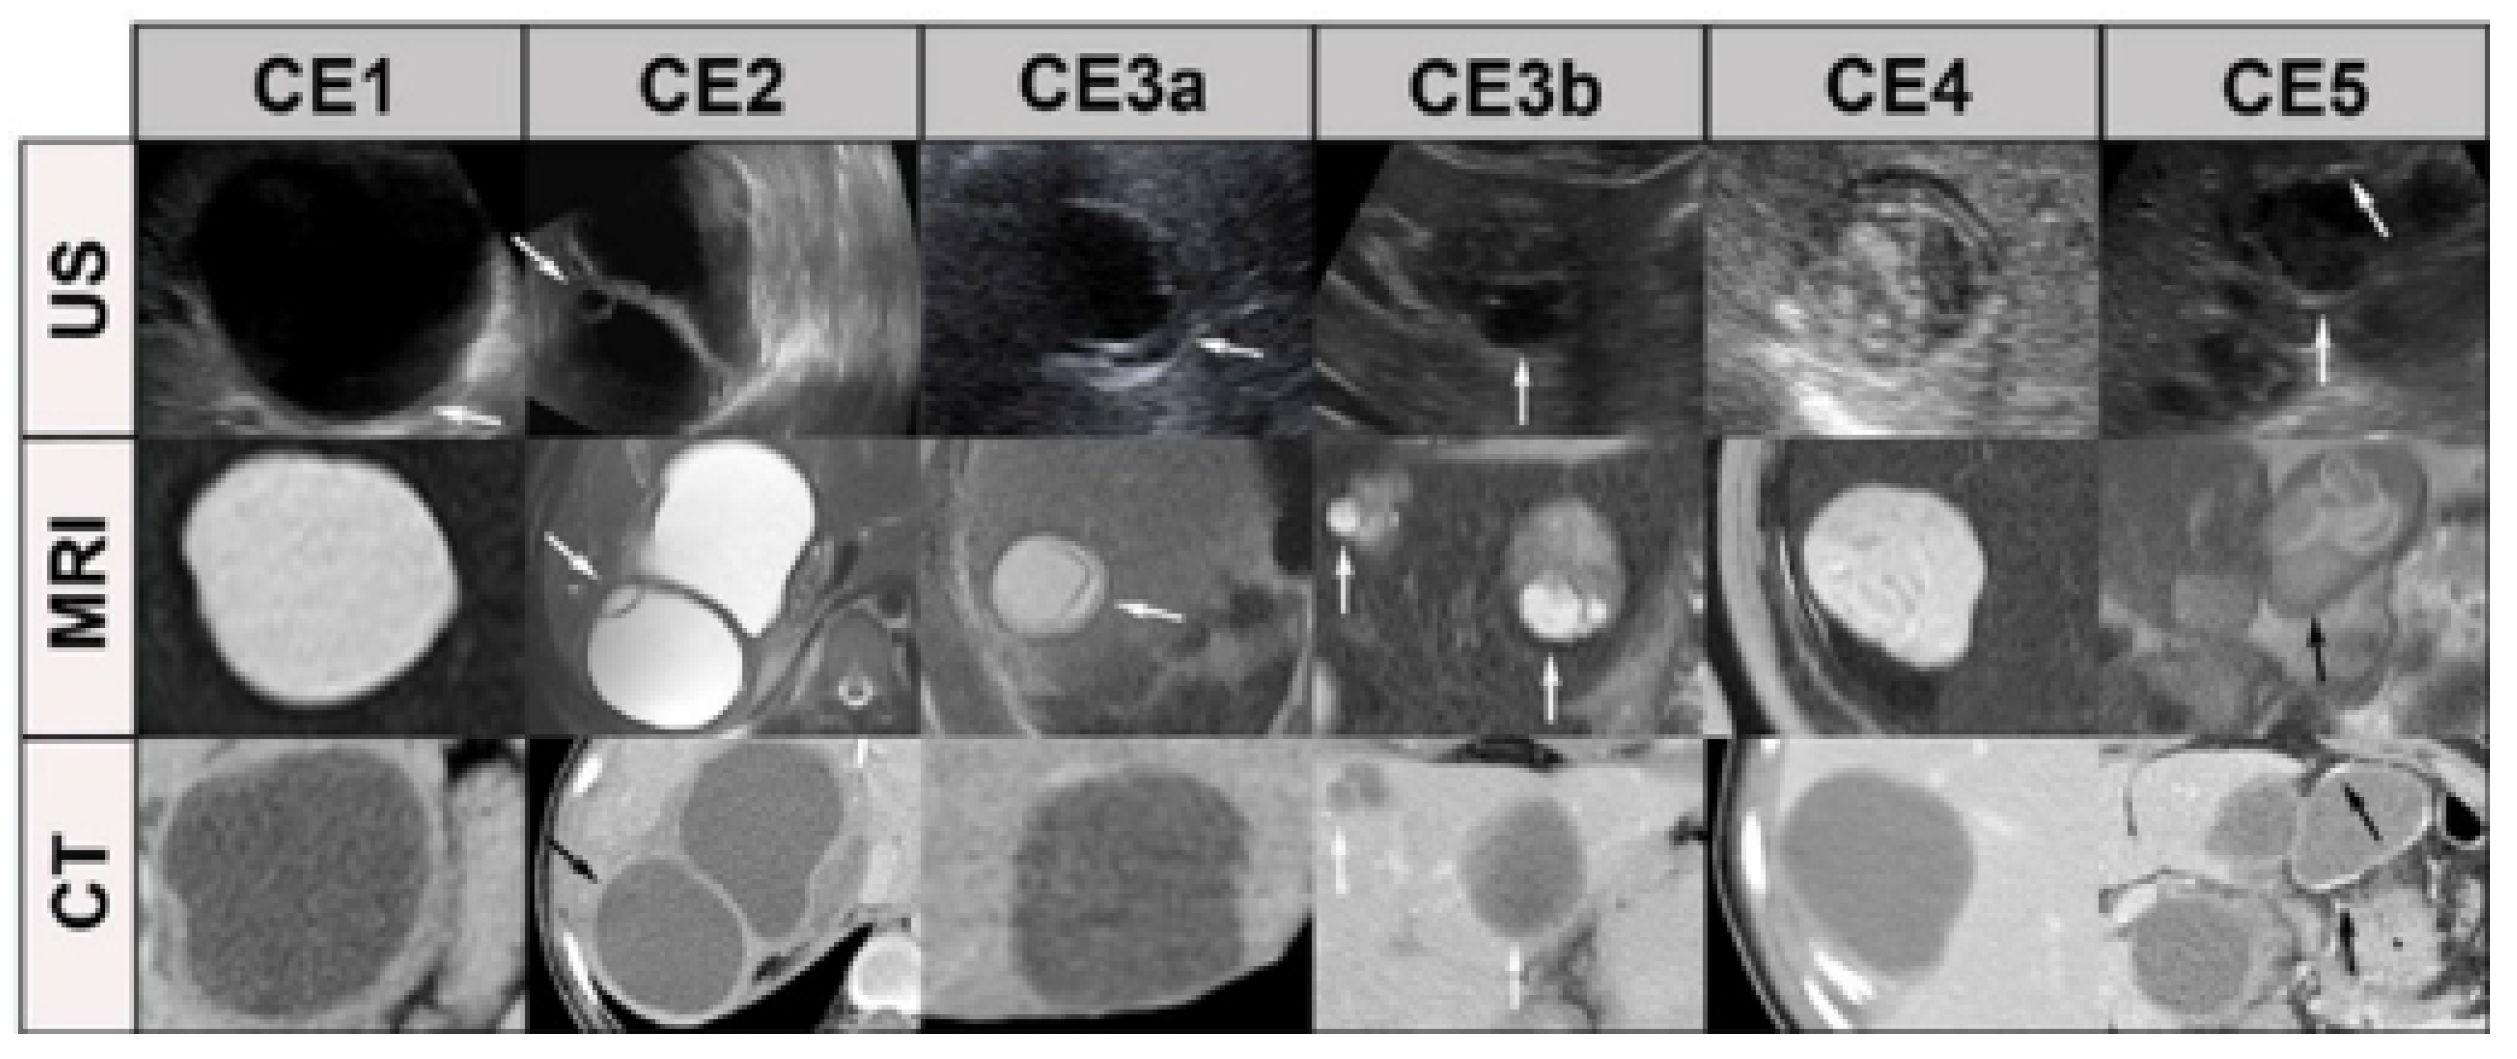

This system was later refined by the WHO in 2001, resulting in the WHO-IWGE standardized classification that is given below (see Table 2). As per the recommendations of the WHO [21], cysts of unknown origin can be divided into three primary types, which can be further subdivided into five stages according to the progression of the cyst. CE cysts can be classified into three types: “active”, “inactive”, and “transitional”. The CE1 and CE2 cysts are categorized as “active” cysts, while the CE3 cysts are regarded as “transitional”. In contrast, the CE4 and CE5 cysts are categorized as “inactive”.

A cyst that is classified as transitional (CE3) can be further divided into two subcategories: CE3a [22] (with detached endocysts) and CE3b (containing clear vesicles). Some studies have found that CE3a cysts tend to be inactive, whereas CE3b cysts are active. US imaging can also be employed to monitor the progression of the disease. For patients who have undergone treatment, follow-up examinations should be conducted every 3–6 months and then annually thereafter. Our objective was to classify CE based on US imaging using the latest classification system developed by WHO. We found that US imaging is an effective tool for classifying CE cysts. In addition, US imaging can be used to monitor the disease’s progression and the effectiveness of the treatment. Figure 1 shows how the classification aligns across different imaging modalities such as US, CT, and MRI. Each modality complements the others, with US being the primary staging tool, CT providing detailed structural evaluation, and MRI offering additional soft tissue detail.